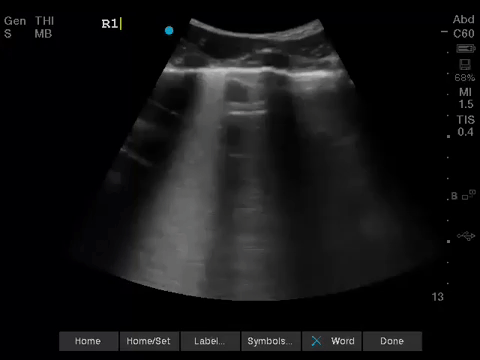

1. When scanning the lungs, a comprehensive, bilateral lung scan is far superior to a single clip; as this will offer more information and permit an interpretation based on the overall pattern of findings. Had this patient only had the R1 area scanned, for example, we may have reached the erroneous conclusion that her hypoxemia was likely due to pulmonary edema.